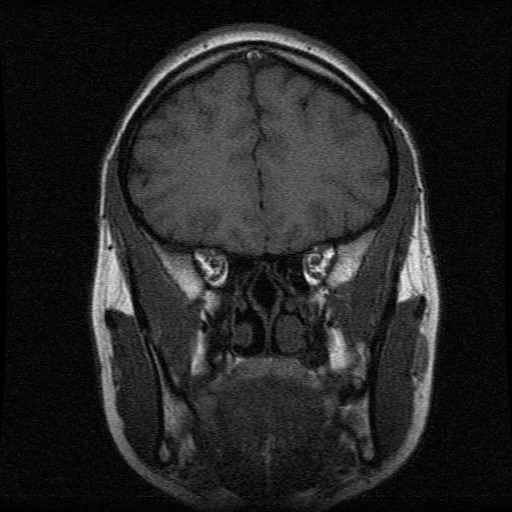

Schedel